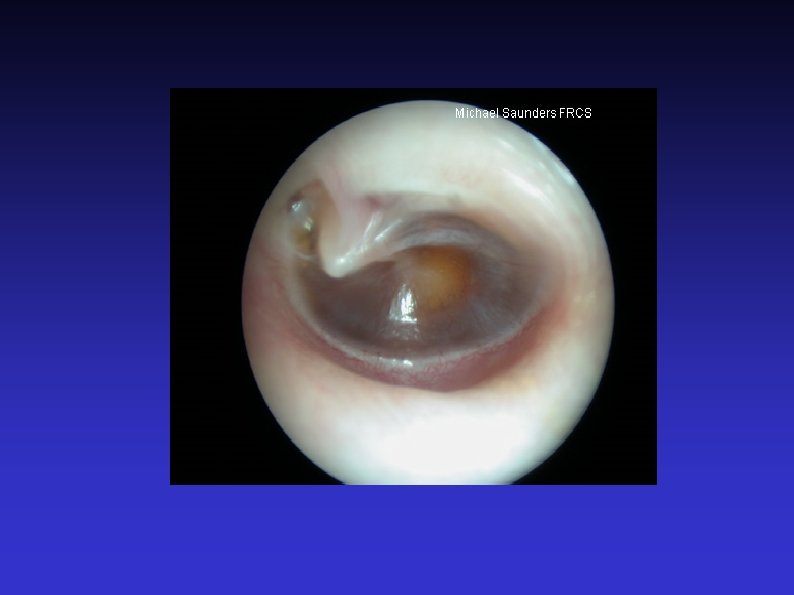

Examination of the Ear 7) Otoscopic examination The lateral process and handle of the malleus lie towards the centre of the tympanic membrane Four quadrants Perforation Central or marginal What can be seen through it Mastoid cavity Dry Wet, inflamed